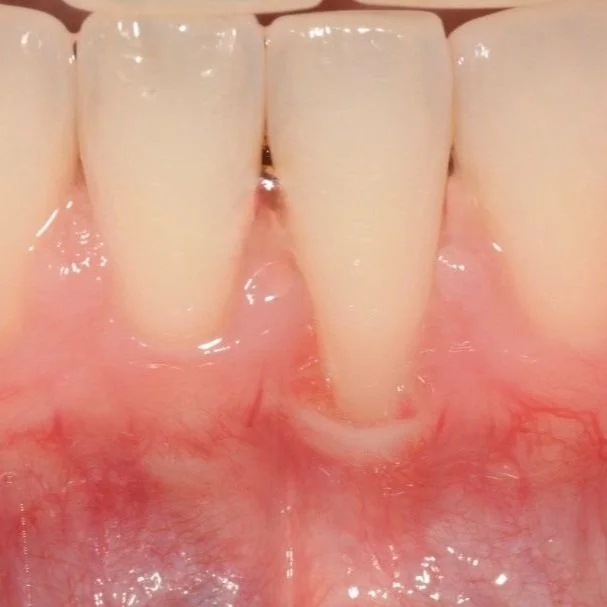

Objectif : Augmenter la quantité de gencive attachée et recouvrir des racines dentaires exposées.

• Sensibilité dentaire

• Inesthétique

• Progression des récessions

• Manque de gencive